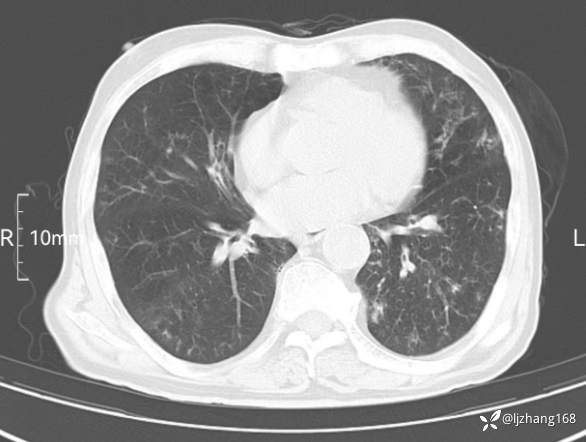

辅助检查:胸部CT:双肺肺气肿,间质性病变,血气分析:PH 7.413, PCO2 29.2mmHg, PO2,81.8mmHg,乳酸 3.3mmol/1,剩余碱-4.0mmol/1,HC03 18.8mmol/1。全血超敏C反应蛋白:超敏C反应蛋白 135.60 mg/L、 白细胞 14x19^9/L,中性粒细胞11.6x10^9/L。